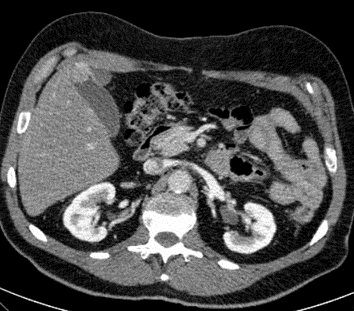

Meme cas en phase veineuse .

Image de rehaussement de contrast en peripherique du

polyp |